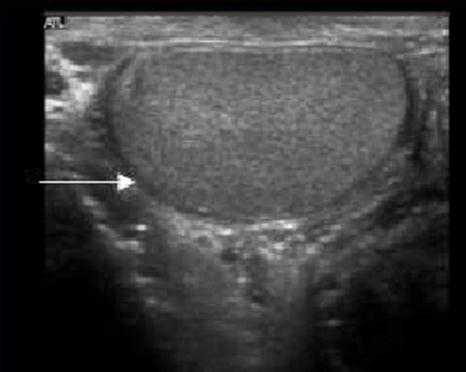

Белочная оболочка яичка на УЗИ представляет собой плотную полоску вокруг яичка. Яичко окружено влагалищной оболочкой, на УЗИ выглядящей как гипоэхогенное кольцо вокруг яичка. Висцеральная пластинка влагалищной оболочки прилежит к яичку и отделена от париетального листка тонким слоем серозной жидкости.

На данном изображении представлен срез яичка в поперечной плоскости. Яичко визуализируется как гомогенное образование, окруженное гипоэхогенным кольцом фиброзной ткани. Это кольцо является влагалищной оболочкой, содержащей между своими листками небольшое количество жидкости.

На ультразвуковом изображении слева визуализируется нормальное яичко, окруженное влагалищной оболочкой. Справа яичко окружено гидроцеле - между париетальным и висцеральным листками находится большое количество жидкости.